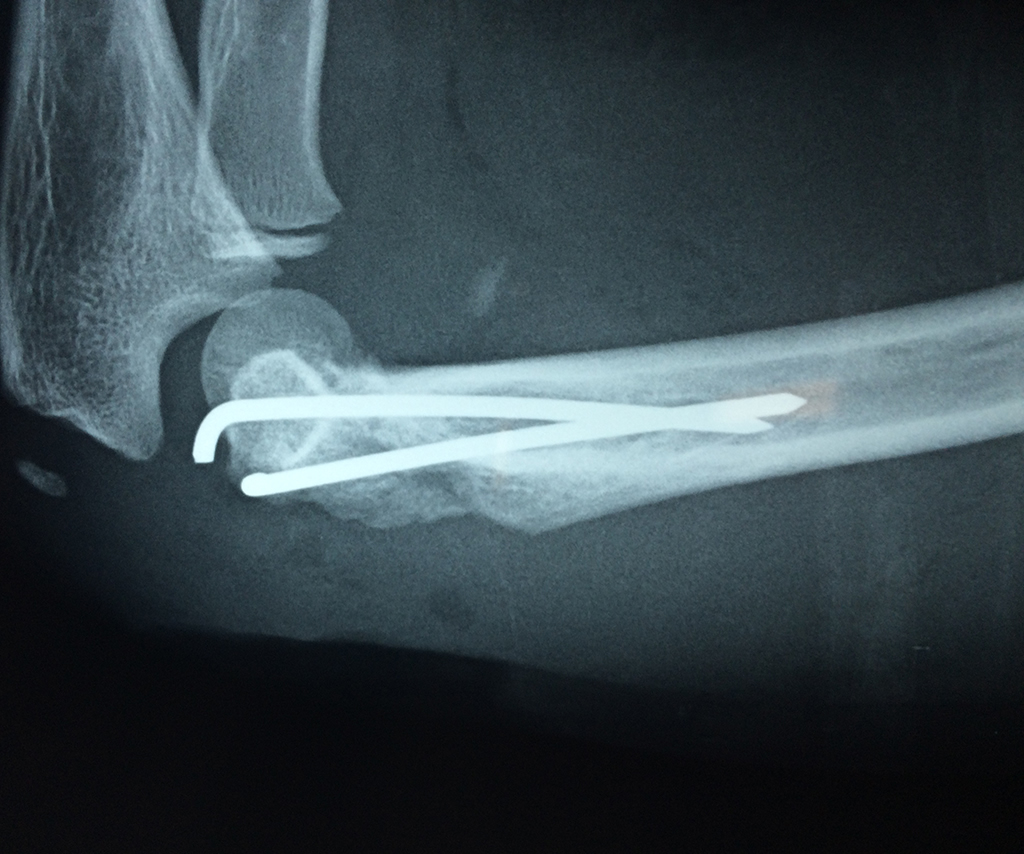

Cirugias en El Salvador - Codo